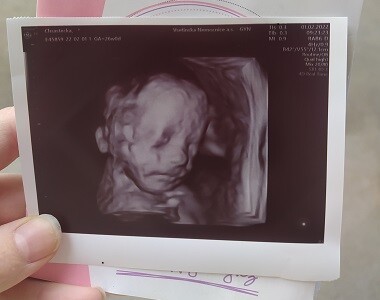

Bára (31. týden těhotenství)